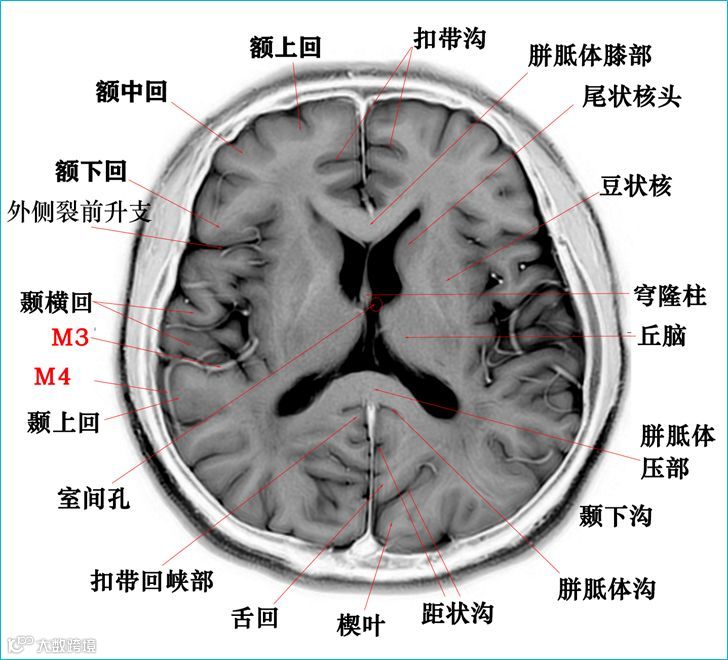

在T2WI反相图学下的颅脑断层解剖(吴晓安老师亲自手动标准)以及标本断层解剖,满满干货,坐在小板凳上,一起学习吧……